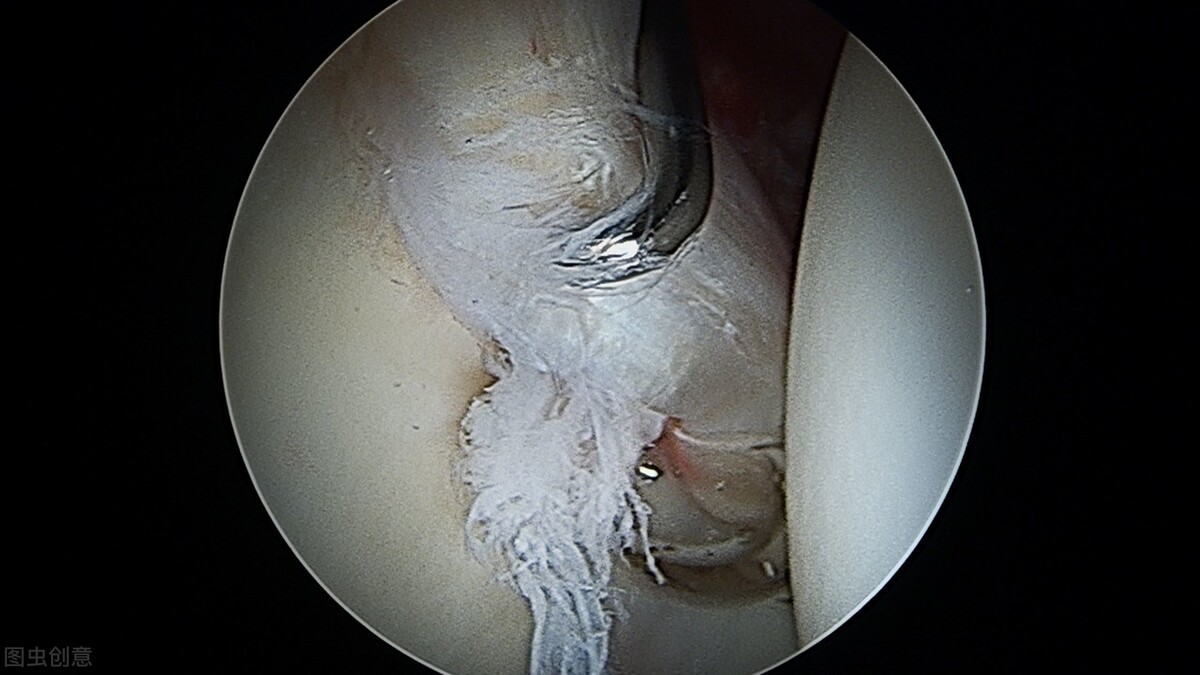

髋关节盂唇撕裂主要由髋关节撞击综合征、运动性损伤、关节脱位引起的,并可导致撕裂者髋部持续疼痛及功能活动障碍,盂唇撕裂的最终诊断以关节镜检查为准,并且关节镜也是最重要的手术治疗方法。日常生活中需要髋关节大幅度、重复运动的项目如足球、高尔夫、田径、跨栏、冰球、瑜伽、跆拳道等运动爱好者容易造成髋关节盂唇损伤。

为了有效治疗髋关节盂唇撕裂,应了解和分辨其损伤的原因:创伤、松弛/活动过度、骨性撞击、发育不良、退行性变等都是引发髋关节盂唇撕裂的因素,上文的患者主要是由于髋关节高能量损伤,髋关节创伤性过度伸展和外旋损伤。盂唇撕裂可分为I型,即盂唇关节囊结合部损伤;II型,即盂唇内损伤。